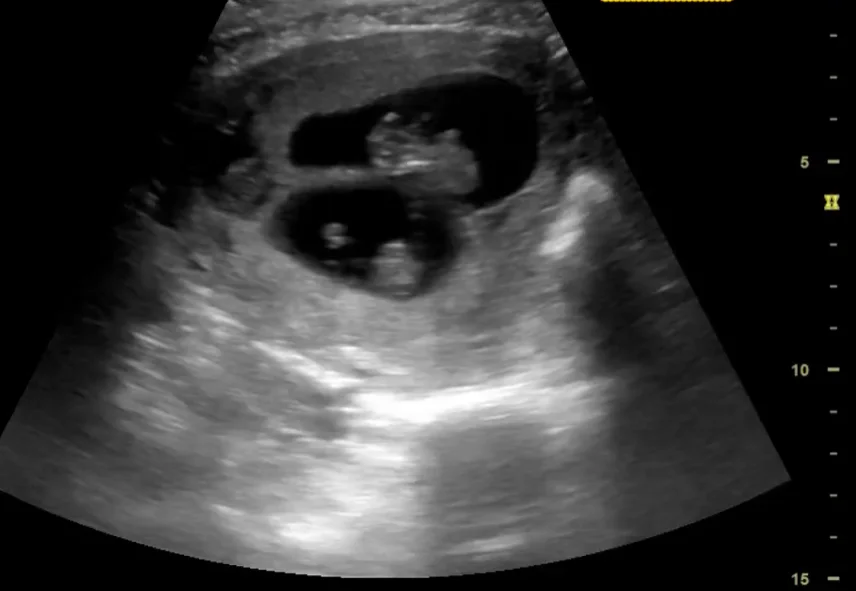

Bánh nhau - túi ối trong song thai (Chorionicity- Amnionicity)